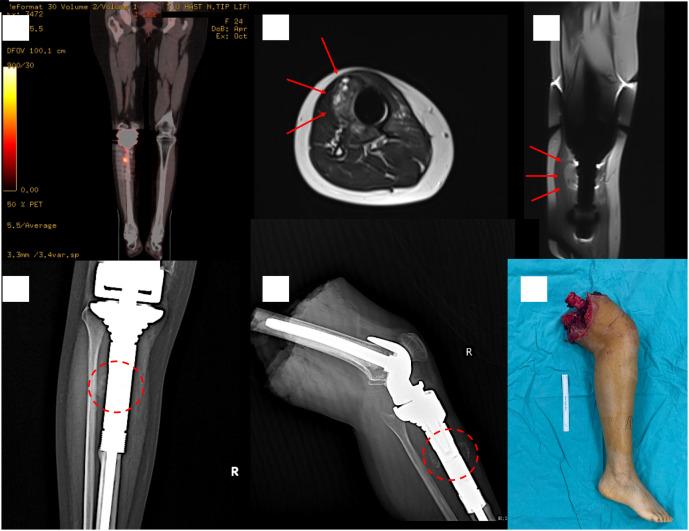

巨细胞富骨肉瘤(GCRO)是一种罕见的骨肉瘤变体,具有不寻常的放射学和组织病理学特征,使其诊断具有挑战性。GCRO最关键和最不寻常的特征是它具有纯粹的溶骨外观。因此,GCRO病例往往因误诊而延误诊断或错误治疗。这对这些患者的预后有负面影响。在本研究中,提出了3例年轻成人病例。第一个病例描述了一位年轻的女性患者,由于误诊为巨细胞骨肿瘤而进行了多次刮除,第二个病例描述了一位年轻的男性患者被误诊为动脉瘤性骨囊肿而延误诊断。最后的病例报告描述了一位年轻女性,她被早期诊断,及时治疗,预后良好。本报告中1例预后不良的病例采用截肢治疗,另1例存活并有多发转移灶。在这种情况下,误诊或延误诊断导致预后不良。为了做出诊断,有必要了解并怀疑这种罕见变异的放射学特征。当处理年轻成人纯干骺端溶骨性病变时,巨细胞富骨肉瘤应作为鉴别诊断选择之一。为了避免误诊或延误,有必要了解并怀疑这种罕见的变异。证据等级:IV级,治疗性研究。

Giant cell-rich osteosarcoma (GCRO) is a rare variant of osteosarcoma with unusual radiological and histopathological features that make its diagnosis challenging. The most critical and unusual feature of GCRO is that it has a purely osteolytic appearance. Therefore, GCRO cases are frequently subject to delayed diagnosis or incorrect treatment owing to misdiagnosis. This negatively affects the prognosis of these patients. In this study, 3 young adult cases are presented. The first case describes a young female patient who underwent repeated curettages due to a misdiagnosis of a giant-cell bone tumor, and the second case describes a delay in diagnosis in a young male patient who was misdiagnosed with an aneurysmal bone cyst. The final case report describes a young woman who was diagnosed early, treated promptly, and had a good prognosis. One of the poor prognosis cases in this report was treated with amputation, and the other was alive with multiple metastases. Misdiagnosis or delayed diagnosis leads to a poor prognosis in such cases. To make a diagnosis, it is necessary to have knowledge and to be suspicious of the radiological features of this rare variant. Giant cell-rich osteosarcoma should be among the differential diagnosis options when dealing with pure metaphysiodiaphyseal osteolytic bone lesions in young adults. To avoid misdiagnosis or delay, it is necessary to have knowledge and to be suspicious of this rare variant. Level of Evidence: Level IV, Therapeutic study.